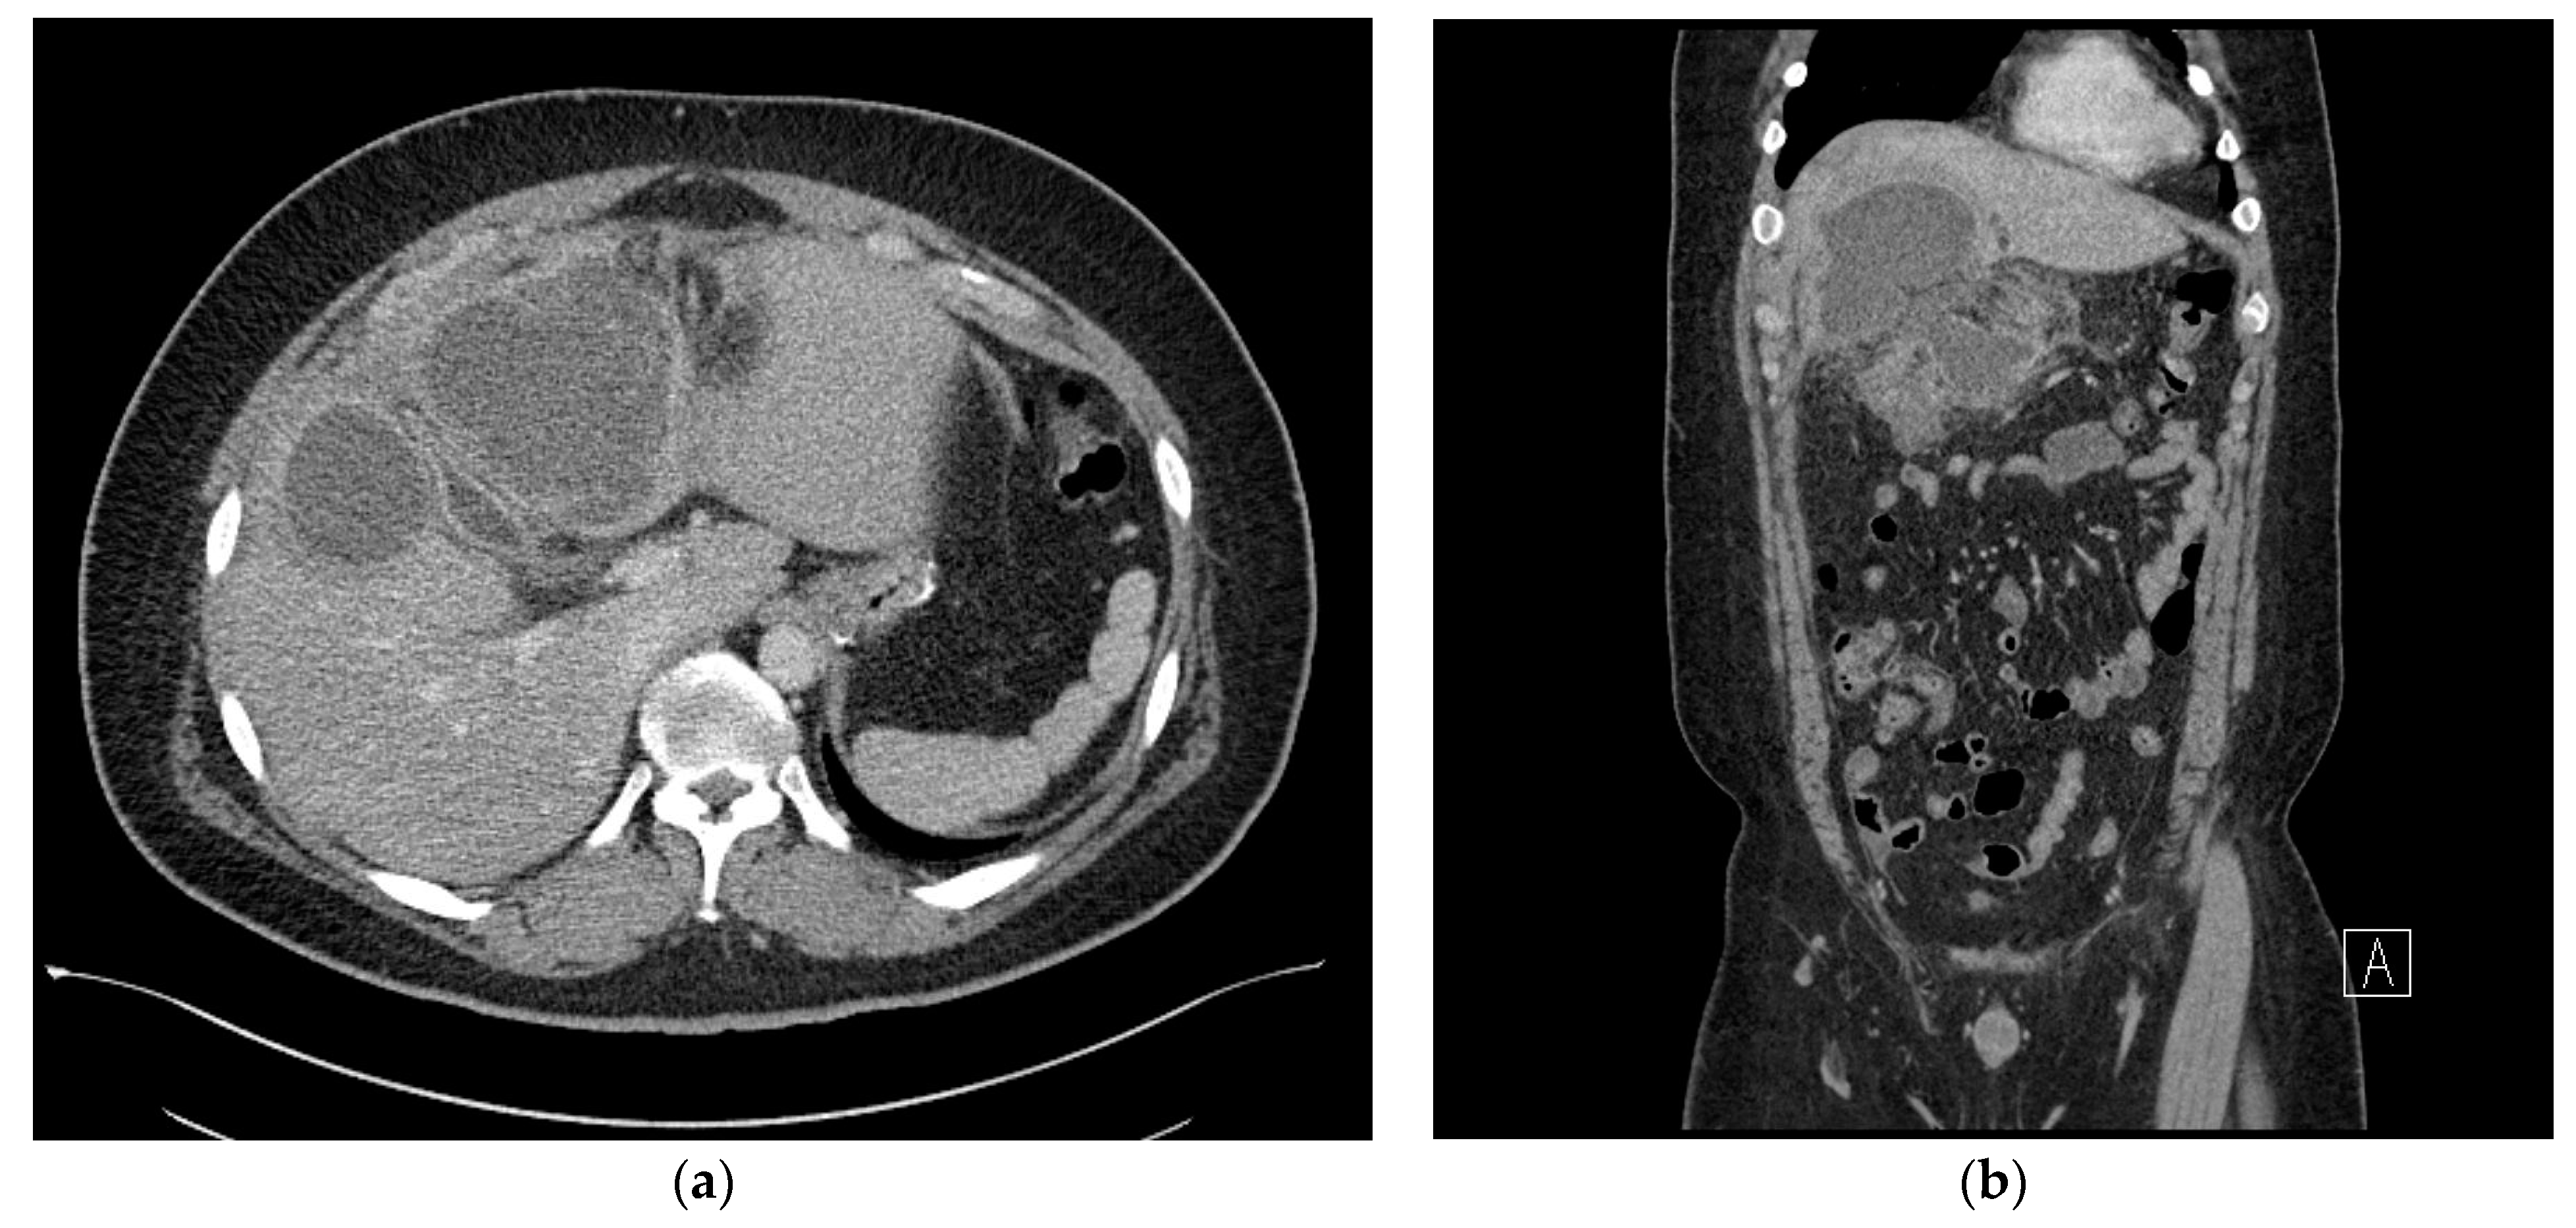

On postoperative day 3, the patient had a fever of 38 °C, WBC count increased to 14.3 × 103/μL, and the C-reactive protein level increased to 23.7 mg/dL. The following day, abdominal CT with oral water-soluble contrast media was performed, which showed a 50 × 40 mm sized abnormal fluid collection in the right subhepatic space. Extra-luminal leakage was not observed (Figure 2b) and apart from the fluid collection in the right subhepatic space (Figure 2a), there was no fluid collection adjacent to the resected stomach. Percutaneous drainage was attempted, but the procedure failed as the needle did not reach the fluid due to the patient’s thick abdominal wall. We decided to observe the patient without the use of antibiotics.

Figure 2. (a) Axial view of the abdominal computed tomography (CT) scan at the subhepatic level, showing a 50 × 40 mm sized abnormal fluid collection in the right subhepatic space. (b) Coronal view of the abdominal computed tomography (CT) scan showing no extraluminal leakage.